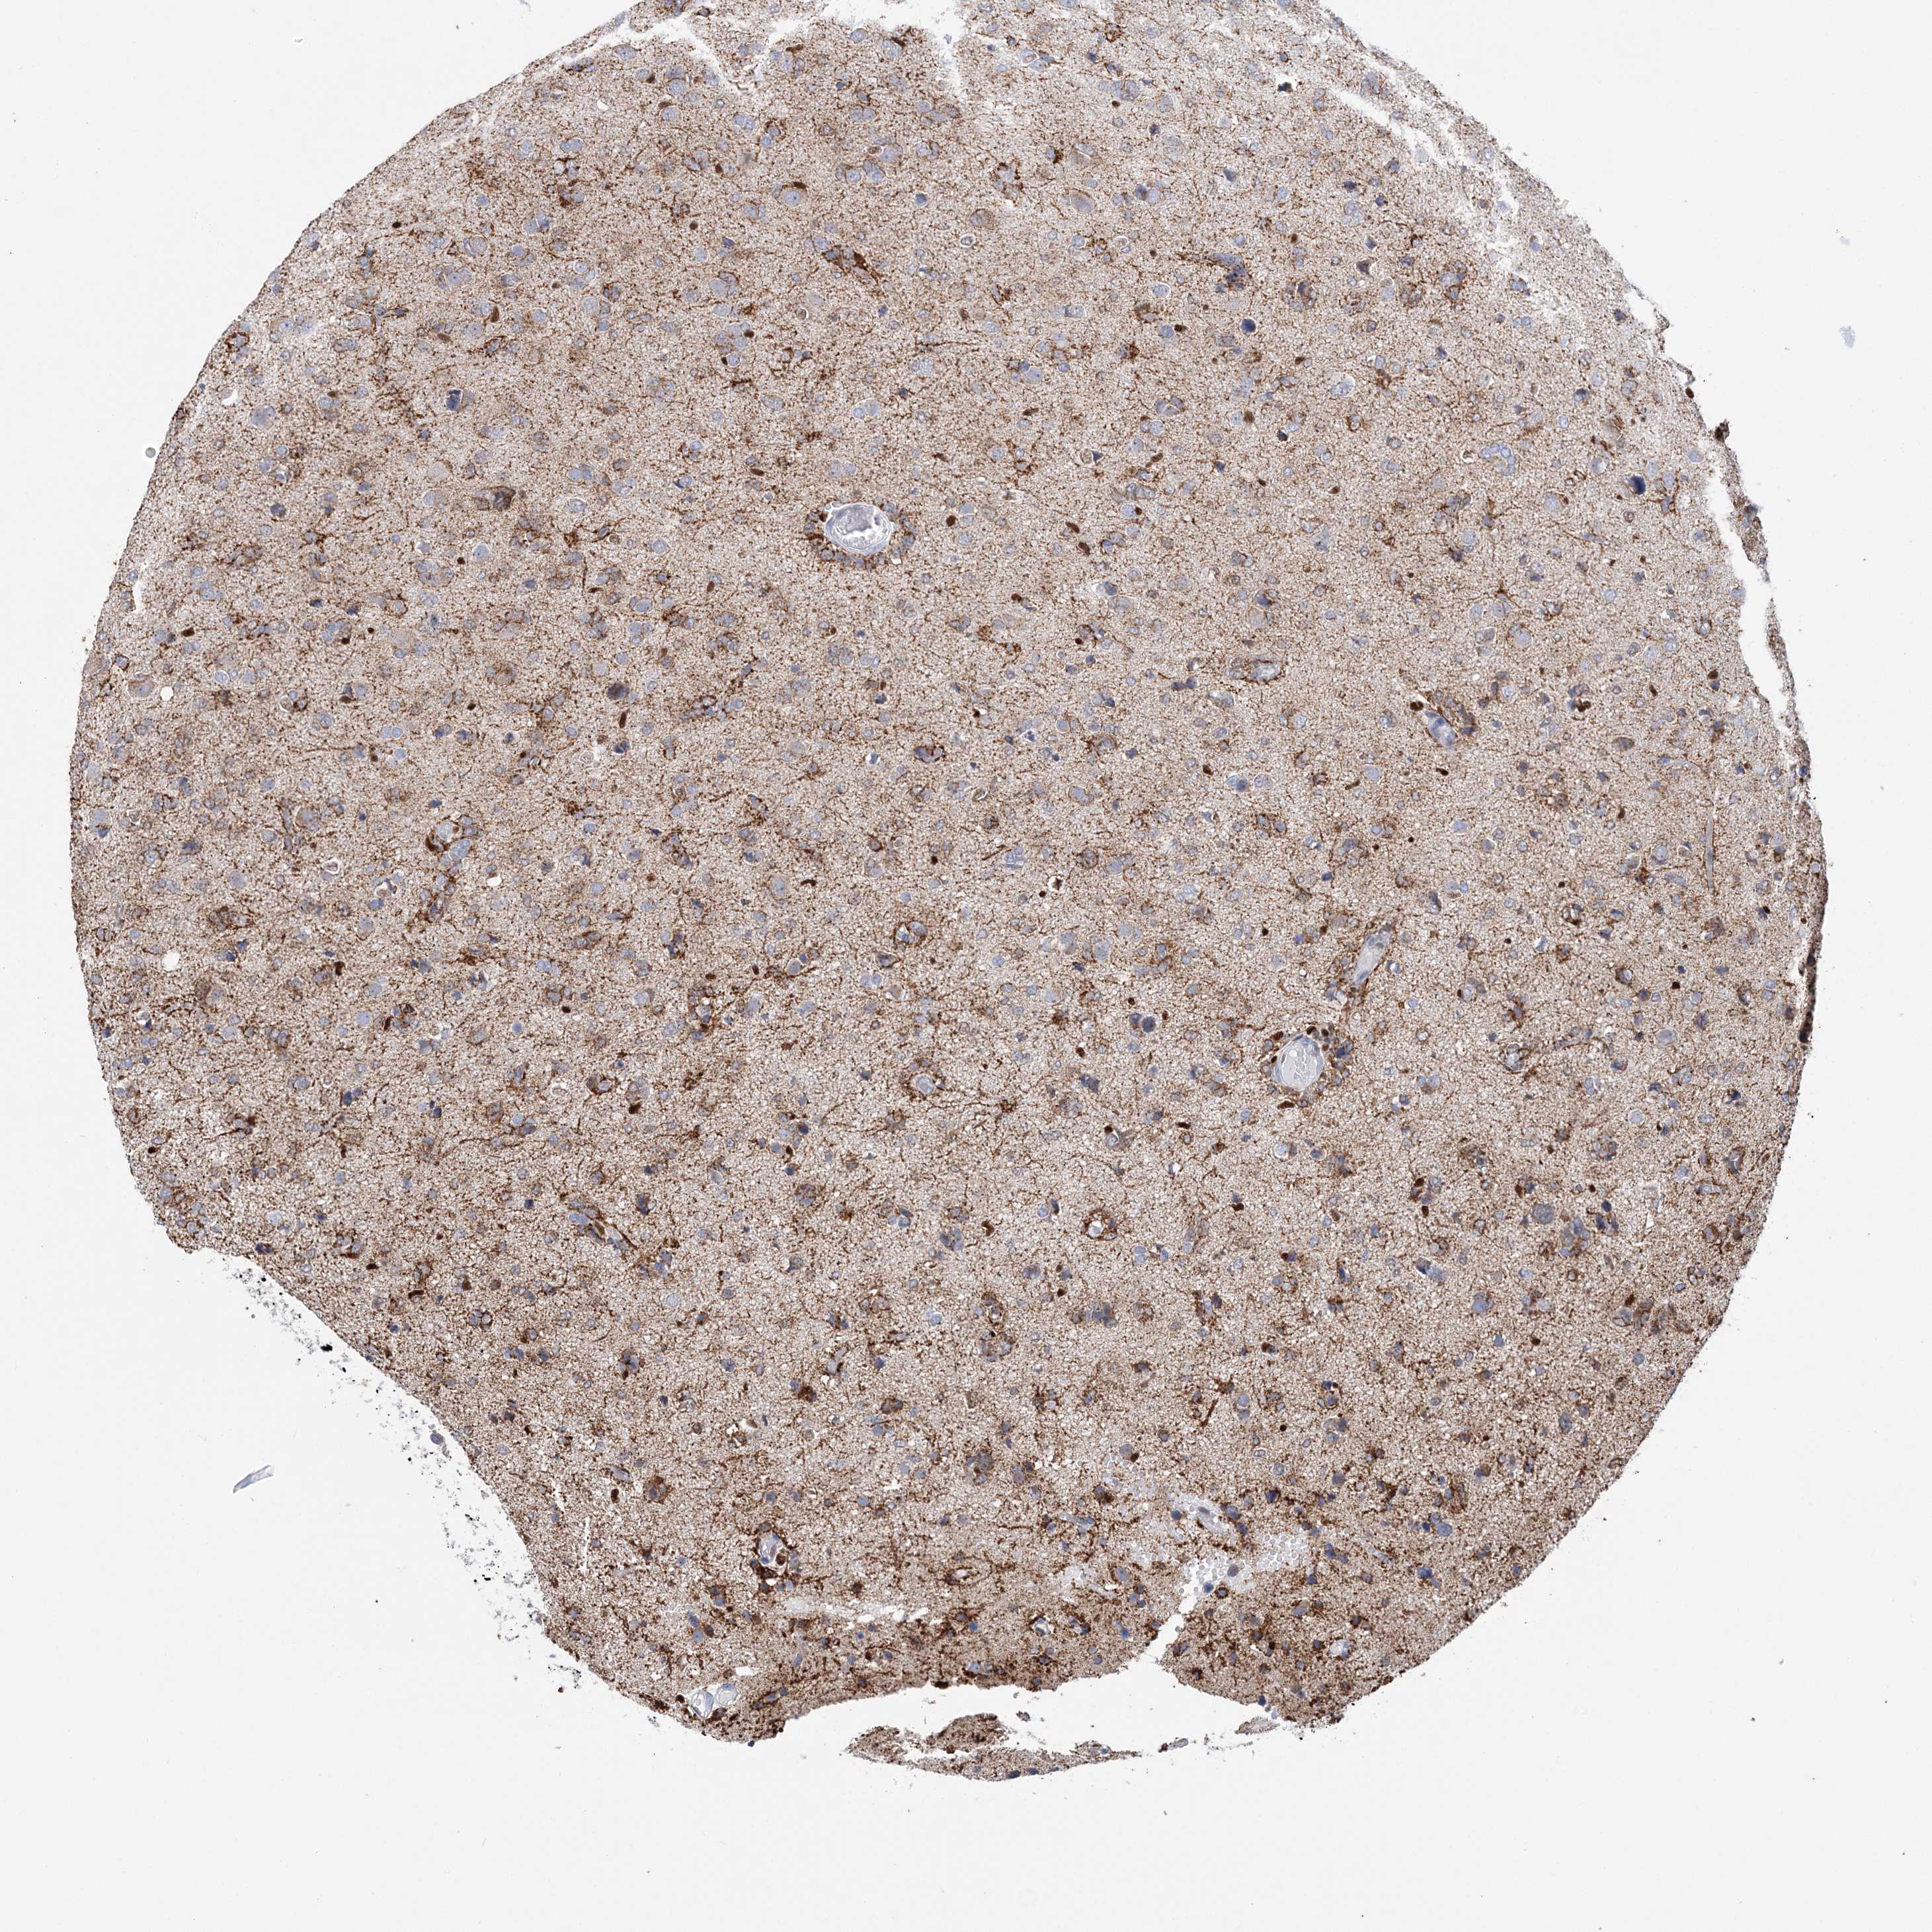

GLIOMA - Protein expressioni

A mouse-over function shows sample information and annotation data. Click on an image to view it in a full screen mode. Samples can be filtered based on level of antibody staining by selecting one or several of the following categories: high, medium, low and not detected. The assay and annotation is described here.

Note that samples used for immunohistochemistry by the Human Protein Atlas do not correspond to samples in the TCGA dataset.

Antibody stainingi

Antibody staining in the annotated cell types in the current human tissue is reported as not detected, low, medium, or high, based on conventional immunohistochemistry profiling in selected tissues. This score is based on the combination of the staining intensity and fraction of stained cells.

Each image is clickable and will lead to virtual microscopy that enables deeper exploration of all samples and also displays staining intensity scores, fraction scores and subcellular localization as well as patient and tissue information for each sample.

Antibody HPA036999

Antibody HPA041289

Staining

High

Medium

Low

Not detected

Intensity

Strong

Moderate

Weak

Negative

Quantity

>75%

75%-25%

<25%

None

Location

Nuclear

Cytoplasmic/membranous

Cytoplasmic/membranous,nuclear

Glioma, malignant, High grade

Glioma, malignant, Low grade

Glioblastoma, NOS